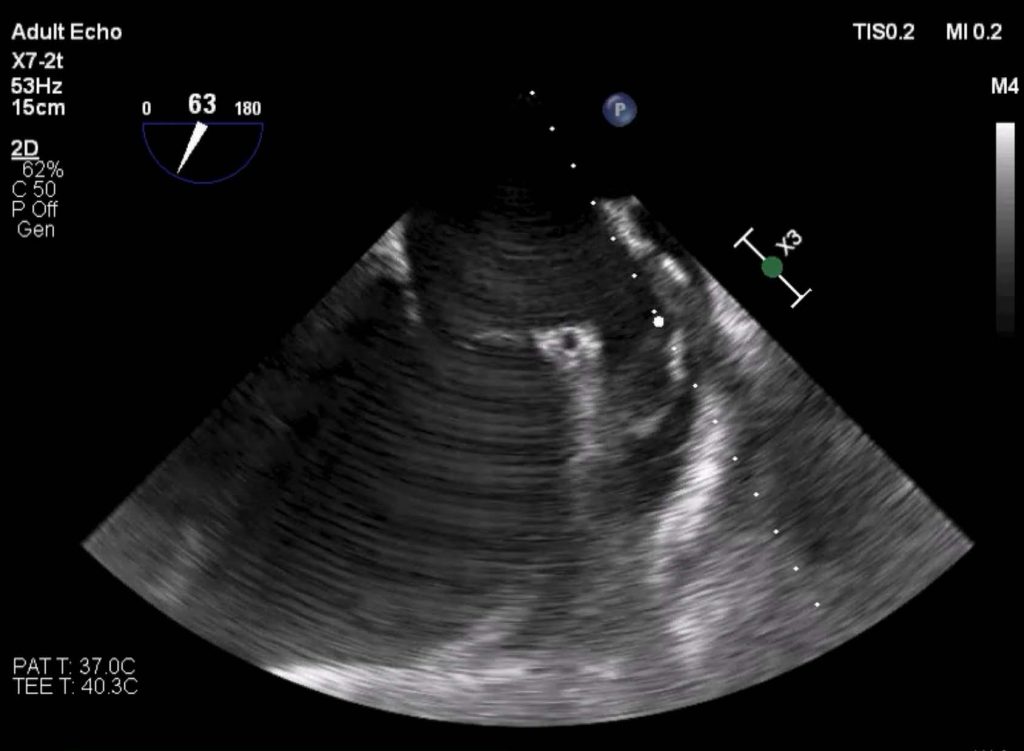

Alternatywą jest echokardiografia przezklatkowa (TTE) – metoda szybka i nieinwazyjna. Choć TTE nie pozwala na bezpośrednie uwidocznienie uszka lewego przedsionka, dostarcza szeregu parametrów hemodynamicznych korelujących z ryzykiem zakrzepowym. Wyzwaniem jest stworzenie modelu, który pozwoli TTE na dostarczanie danych o ryzyku LAT z precyzją zbliżoną do badania przezprzełykowego.

Aby wyeliminować ograniczenia dotychczasowych modeli, które wymagały ręcznego wprowadzania licznych parametrów , wdrożyliśmy w pełni zautomatyzowany system analizy nagrań wideo z echokardiografii przezklatkowej (TTE) oparty na głębokich sieciach konwolucyjnych. Zastosowanie tego rozwiązania pozwala na eliminację błędów wynikających ze zmienności międzyobserwacyjnej, znacząco poprawiając powtarzalność wyników. Ponadto, sztuczna inteligencja umożliwia ekstrakcję ukrytych cech hemodynamicznych, takich jak prędkość przepływu w uszku lewego przedsionka (LAAV), których nie można tradycyjnie zmierzyć w badaniu TTE.

Krok 1: Ekstrakcja cech i automatyczna segmentacja

Wykorzystując referencyjny zbiór danych EchoNet, zawierający 10 030 nagrań z echokardiografii przezklatkowej (TTE), model sztucznej inteligencji oparty na architekturze U-Net lub Echonet-Dynamic dokonuje automatycznej segmentacji lewego przedsionka (LA) i lewej komory (LV). Pozwala to na wygenerowanie krzywych pola powierzchni w czasie (area-time curves) , które precyzyjnie opisują rozmiar i funkcję jam serca.

Krok 2: Predykcja LAT i modelowanie LAAV

W drugim etapie model integruje wygenerowane przez AI dane obrazowe z kontekstem klinicznym, obejmującym choroby współistniejące oraz farmakoterapię. Istotnym elementem projektu jest wykorzystanie uczenia maszynowego do jednoczesnej predykcji obecności skrzepliny (modele klasyfikacyjne) oraz szacowania prędkości przepływu w uszku lewego przedsionka (LAAV – modele regresyjne). LAAV jest kluczowym, ilościowym parametrem zastępczym (surogatem) ryzyka zakrzepowo-zatorowego , którego obecnie nie można zmierzyć lub oszacować za pomocą standardowego badania TTE i który dotychczas wymagał przeprowadzenia bardziej inwazyjnego badania przezprzełykowego (TEE).